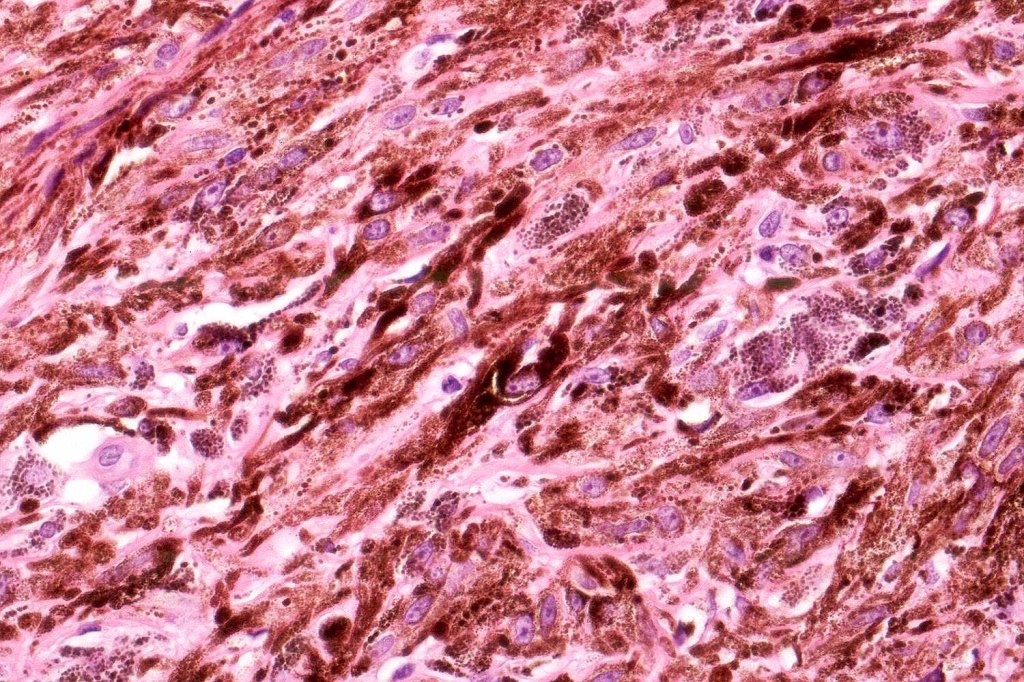

•Admixture of spindle cells, pigmented bipolar or dendritic cells & melanophages

•Cytoplasm is pale and nuclei are small with inconspicuous nucleoli

•An alveolar pattern is characteristic particularly with clear cell nodules

•Multinucleate giant cells sometimes present

•Balloon cell change